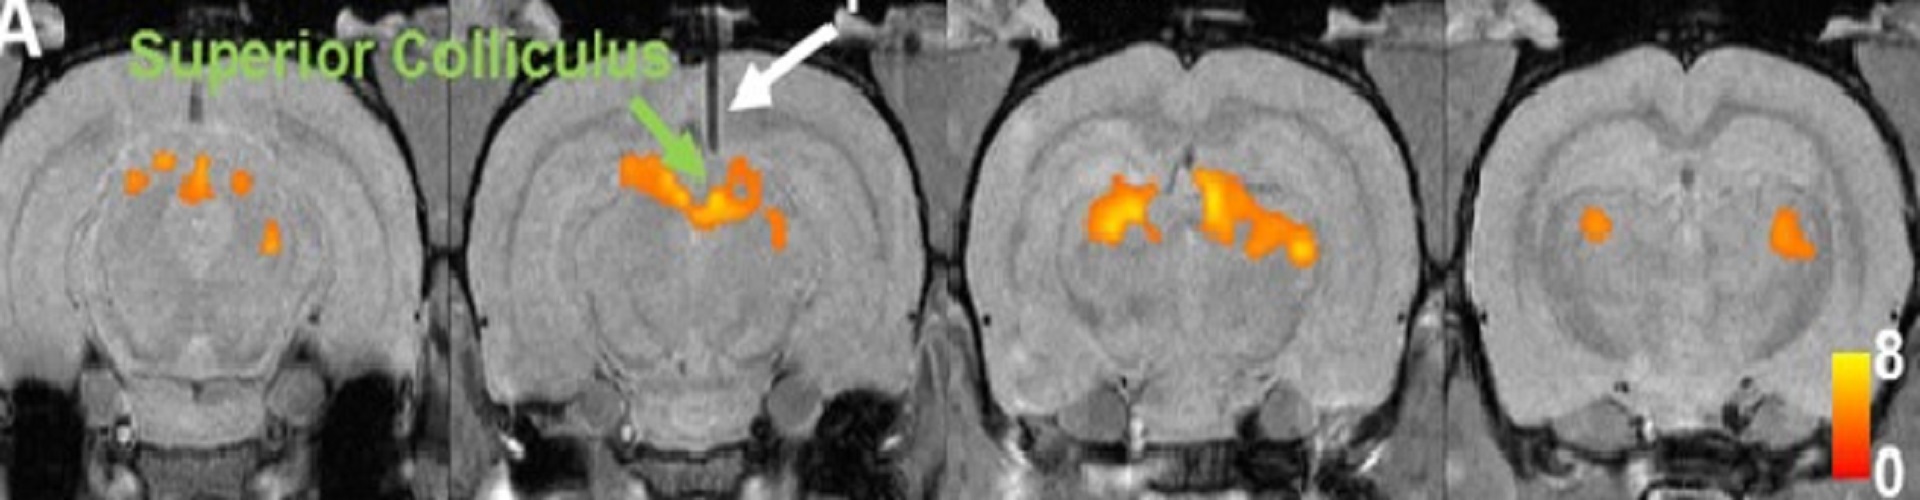

与磁共振高度兼容的电极促进解析深部脑刺激治疗机理

脑影像图1